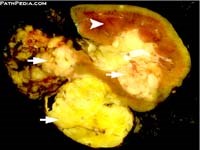

Không thể kết luận bản chất khối u là gì, chúng tôi đề nghị bệnh nhân nên chuyển vào Trung tâm chẩn đoán y khoa Hòa Hảo, thành phố Hồ Chí Minh để xác định thêm bằng siêu âm, CT và MRI cũng như sinh thiết bản chất nếu có thể. Kết quả tại TT chẩn đoán y khoa Hòa Hảo kêt luận là u dạng angiomyolipoma trên thận (P) và các cơ quan khác không có. Bệnh nhân đưa kết quả quay trở lại Viện Sốt rét KST-CT Quy Nhơn, sau đó bác sĩ ở đây liên hệ cho bệnh nhân sang một BV tại Singapore để can thiệp phẩu thuật và làm giải phẩu bệnh cũng cho ra là u angiomyolipoma, chẩn đoán phân biệt là u lao xơ hóa. Mổ cắt bỏ khối u kích thước 6.0 x 8.3cm, đang có dấu hiệu xuất huyết bên trong u do 3 điểm phình mạch nhỏ trên hệ mạch dọc theo dẫn đến u và kèm theo cắt toàn bộ thận vì khối u xâm lấn và nguy cơ suy thận đến gần. Không làm nút mạch vì u quá lớn.

Một khối AML gồm các tế bào mạch máu, tế bào cơ trơn chưa trưởng thành và tế bào mỡ với các tỷ lệ khác nhau. Cả ba thành phần này lần lượt ghép tên hình thành nên khối u có tên gọi như trên là: angio-, myo- và lip-. Tiếp vị ngữ -oma có nghĩa là khối u. Angiomyolipoma điển hình hay phát hiện trong tạng thận nhưng cũng có thể gặp trong gan và ít gặp hơn ở buồng trứng, vòi trứng, dây thừng tinh, đại tràng và vòm.